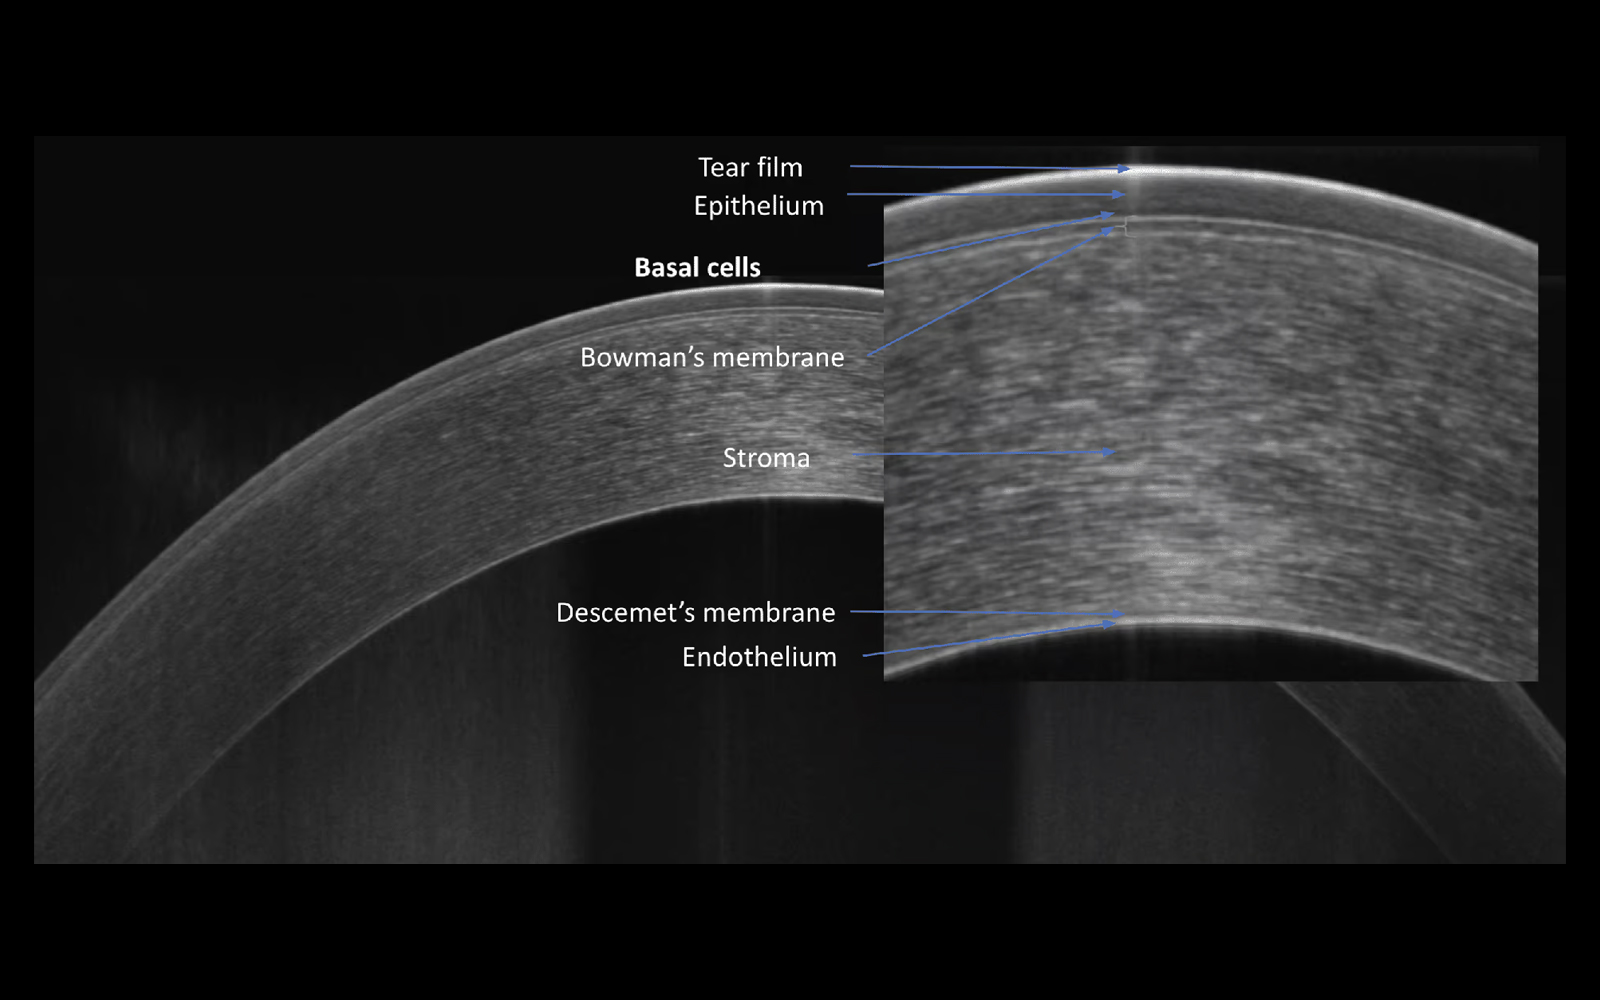

The system provides 3 µm resolution imaging, enabling detailed visualization of fine ocular structures and improved detection of subtle pathological changes.

The combination of super-fast scanning at 130,000 scans per second and 3 µm High Resolution will provide a powerful tool for optimising precision, accuracy and improving the detection of the smallest lesions in tissue.

With a unique combination of super-fast scanning at 130,000 scans per second and ultra-high 3 µm resolution, this powerful device takes precision, accuracy, and detection of even the finest lesions to a whole new level.

Cornea and Epithelium

Comprehensive anterior segment imaging enables detailed visualization and assessment of corneal and anterior eye structures within the same OCT workflow — without the need for additional hardware or adapters.

The system supports high-resolution imaging and quantitative analysis of the anterior segment, providing valuable data for diagnosis, treatment planning, and follow-up.

AI-supported analysis of the anterior segment enables detailed evaluation of corneal structures, including epithelium and pachymetry.

Presentation of results for both eyes supports quick and precise assessment, while epithelial and pachymetry maps are included as part of the standard package.